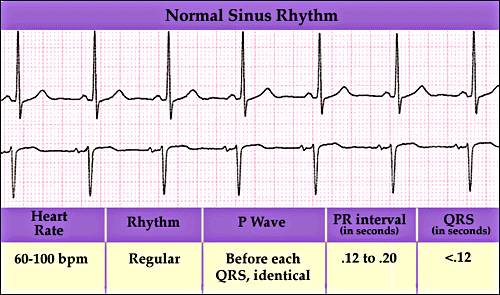

TULBURARI DE RITM

TULBURARI DE RITM In conditii fiziologice, centrul de comanda al inimii este NSA, care emite impulsuri cu o frecventa de 70-80/min Aceste impulsuri se propaga prin sistemul excito-conductor spre miocard In conditCiteste tot ... 1349 cuvinte

Dimensiune mica

+ cu imagini |

TULBURARI DE CONDUCERE

TULBURARI DE CONDUCERE Reprezinta tulburari in propagarea excitatiei de la un teritoriu cardiac excitat spre un teriu vecin neexcitat Clasificarea topografica imparte tulburarile de conducere in: sino-atriale, atriCiteste tot ... 954 cuvinte

Dimensiune mica

+ cu imagini |